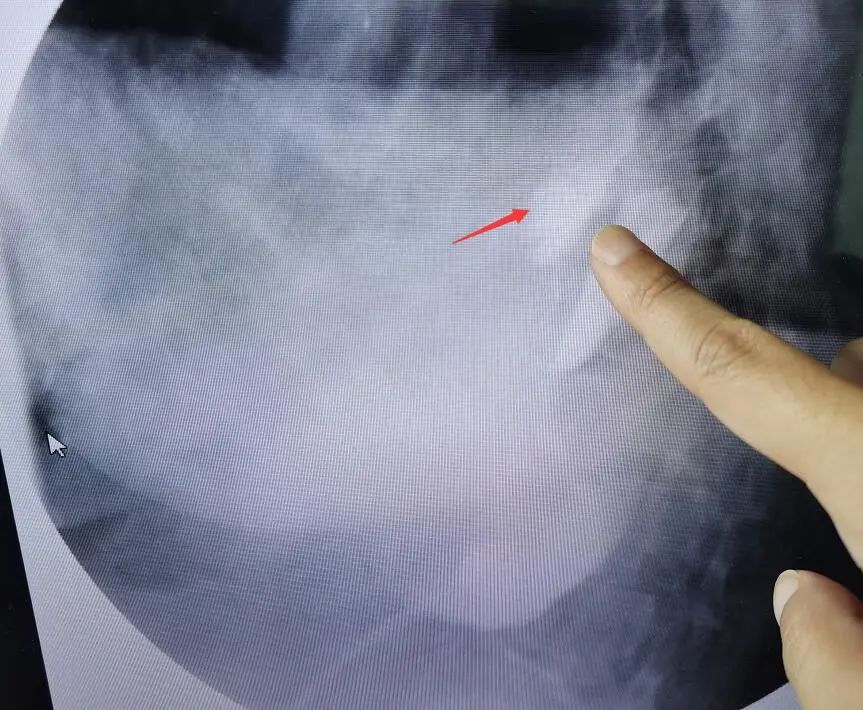

食管造影能夠清晰地看到造影劑漏入胸腔

根據(jù)自己多年的工作經(jīng)驗,瑞慈醫(yī)院副院長、胸外科主任曹飛接診患者后,第一時間想到了自發(fā)性食管破裂。食管造影檢查顯示,果不其然:食管中下段破裂。